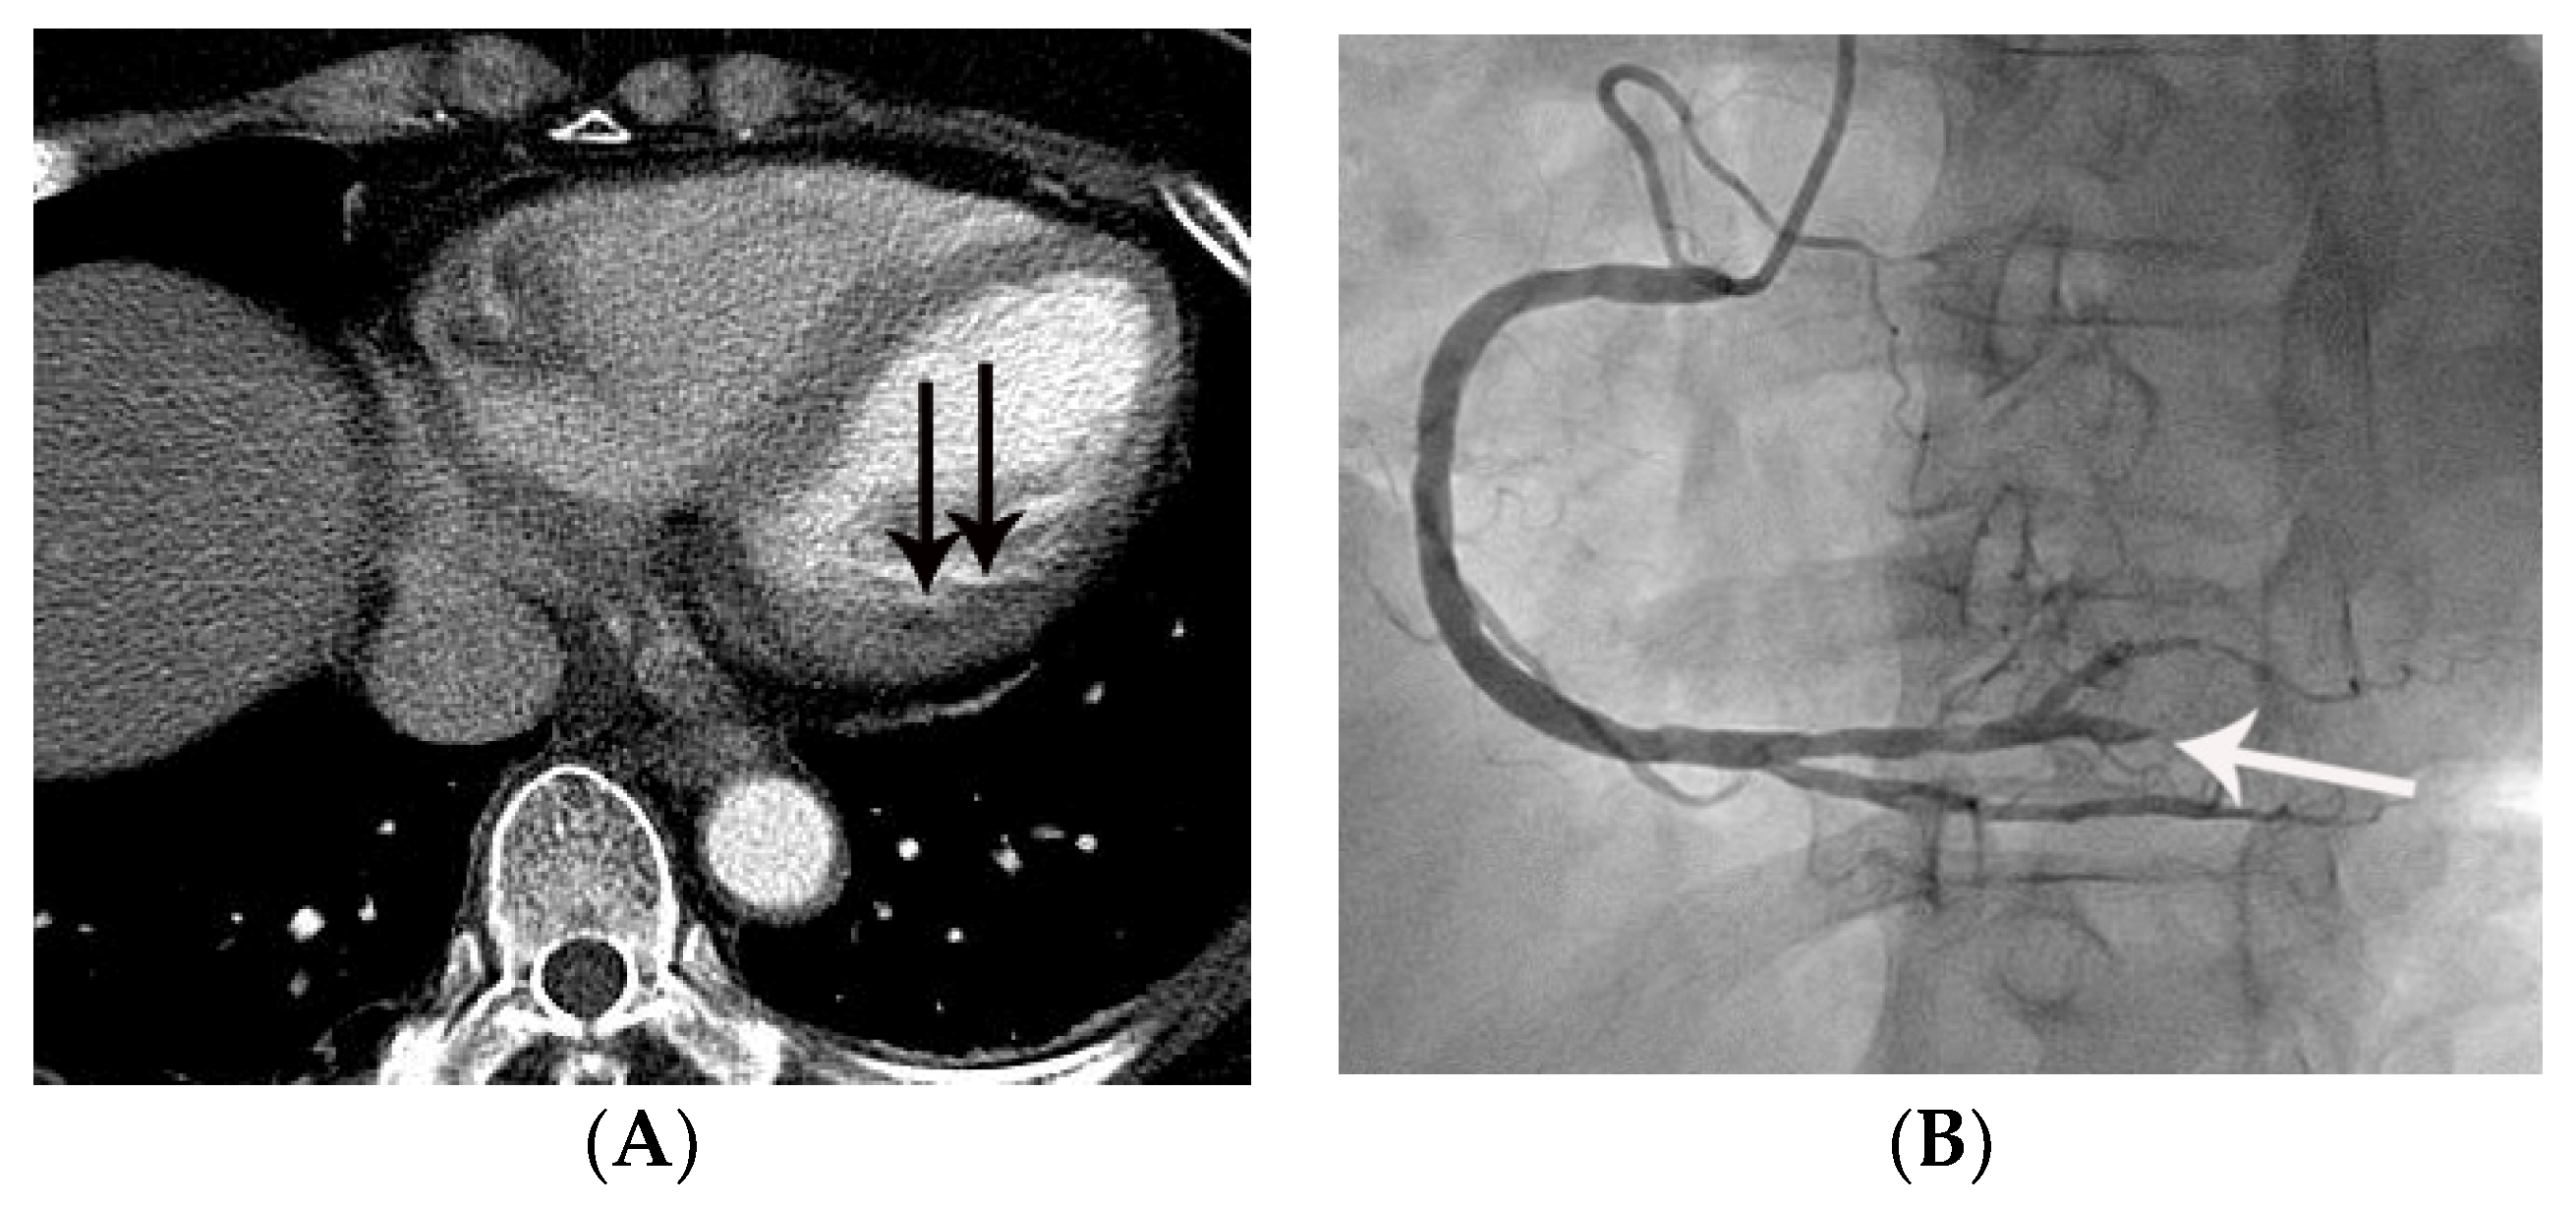

Figure 4.

False negative diagnosis of acute myocardial infarction on non-gated chest CT in a 67-year-old female with a small acute myocardial infarction. (A) Equivocal MPD (CT score of 1 for myocardial perfusion defect (MPD)) (arrow) was noted in the basal lateral segment of the left ventricle on an axial image. (B) Subsequent coronary angiography showed total occlusion (arrow) of the posterolateral branch of the right coronary artery, suggesting a culprit lesion. Note that it was difficult to differentiate true MPD from artifacts in this case.